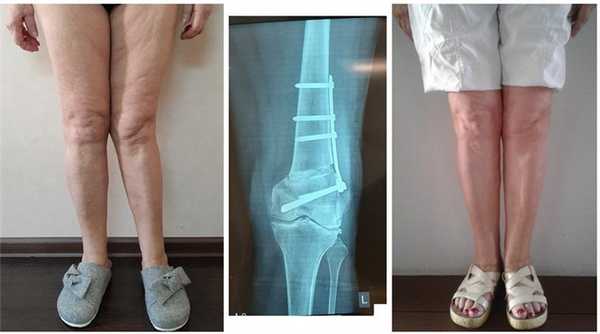

Женщина 24 лет. Варусная деформация коленных суставов. Слева - до операции. Справа - после корригирующей остеотомии.

Женщина 21 года. Вальгусная деформация коленных суставов. До и после корригирующей остеотомии.